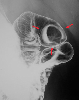

A case of carcinoid tumor which developed in the duodenal bulb.

X-ray